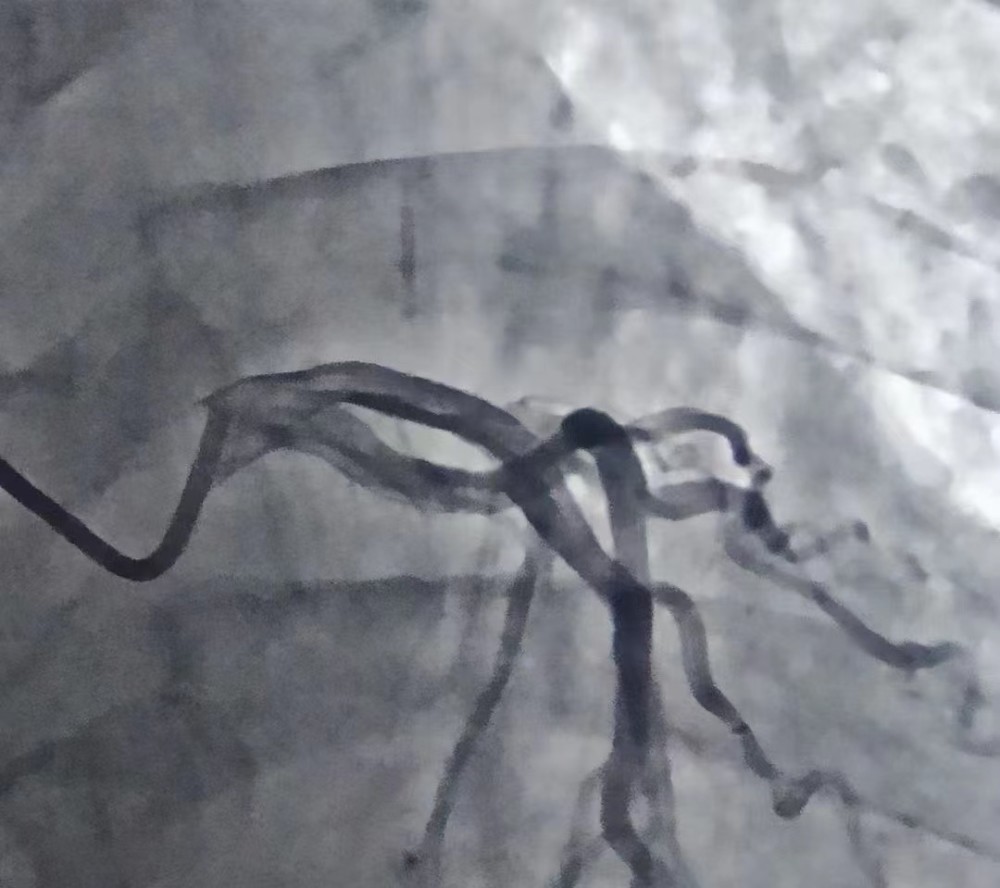

如果糖尿病朋友发现自己有这些症状,就要进行冠状动脉造影检查来确定动脉狭窄或者阻塞的程度,同时积极进行抗血小板、溶栓等治疗,必要时可以植入冠脉支架或者搭桥治疗。